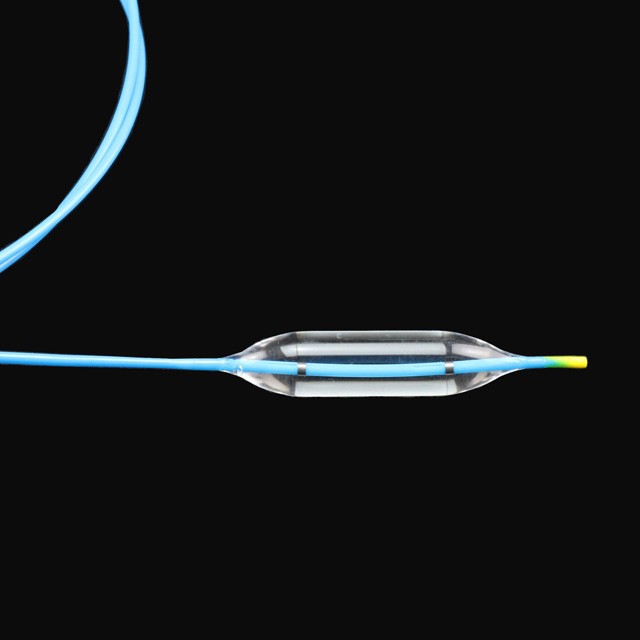

● ፊኛው በተለየ ጫና ውስጥ በሦስት የተለያዩ ዲያሜትሮች ውስጥ ለሐኪሞች ብዙ ምርጫዎችን በመስጠት ለሐኪሞች የበለጠ ምርጫን በመስጠት .

● የተጣራ ለስላሳ ጫፍ ንድፍ, ይህም በትንሽ ጉዳት ወደ target ላማው ቦታ የሚገባ .

● ፈጣን የፍሳሽ ማስወገጃ ንድፍ የቀዶ ጥገና ጊዜን ለመቀነስ ይረዳል .}

● የባለቤትነት በሁለቱም ጫፎች ላይ የሬዲዮአክሲክ አመልካቾች በ x-Ray {{1} ስር ትክክለኛ አቀማመጥ ሊያቀርቡ ይችላሉ